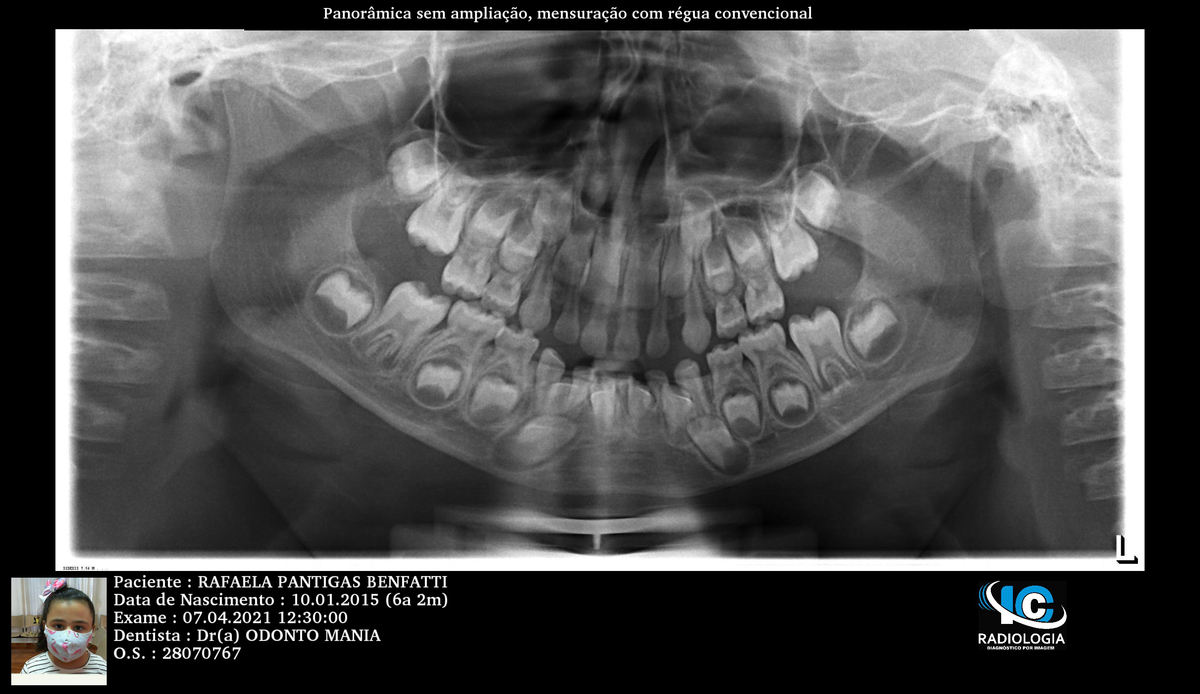

R.P.B.

ORTODONTIA MIOFUNCIONAL